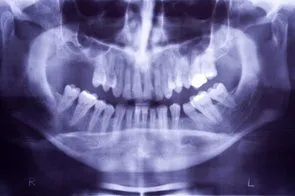

• Panorex

Loss of posterior teeth may result in excessive forces being placed on your remaining teeth. Fortunately, the use of dental implants and crowns allow you to replace these missing teeth. However, the position of the sinus in the upper posterior areas may be too low for proper placement of dental implants.

A simple procedure allows the sinus floor to be repositioned, creating enough space to properly place an implant. Various grafting materials are used to encourage your bone to grow more quickly into the area, helping to stabilize the dental implant. Replace with your own bone in this area the grafting material as it grows into the area.

Under certain conditions, an even simpler procedure can be utilized. When possible, the bone remaining under the sinus floor is gently “pushed up”, thus lifting the floor of the “dropped” sinus. Bone replacement materials are then placed beneath this lifted bone. Once again the bone materials are replaced as your body grow new bone into this area.

Sinus augmentation procedures are highly predictable, with studies reporting over 95% success. Following sufficient healing of a sinus augmentation (6-10 months), implants are placed in a predictable and successful manner. It is important to realize that if the sinus augmentation procedure does not result in enough bone for implant placement, additional bone may be regenerated through a second sinus augmentation procedure at the time of implant placement.